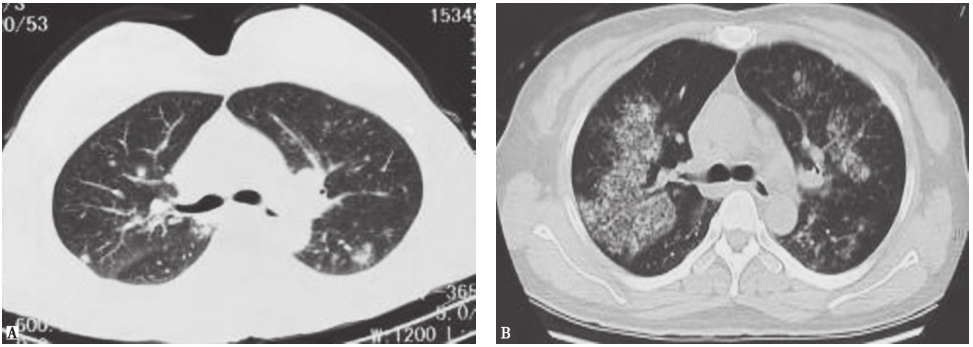

图6高分化腺癌胸部CT表现

男性患者,37岁,因咳嗽9个月入院,病理检查证实为高分化腺癌。胸部CT表现为两肺野多发斑点状、斑片状结节影及模糊环状低密度影,病灶形态欠光整

诊断明确后,嘱患者严格戒烟,同时给予糖皮质激素治疗(因合并骨质损害)。患者胸痛症状明显好转,1个月后复查胸部CT示肺部病灶基本吸收(图9)。

图9复查胸部CT表现

PLCH目前尚无标准治疗指南,患者预后也不尽相同。部分病例通过严格戒烟可能自愈,糖皮质激素对于部分有症状的患者有效。联合化疗用于LCH严重累及多系统者。对于急性进展并且出现呼吸衰竭的患者,可以进行肺移植术。本例患者行经皮肺穿刺活检明确诊断后,鉴于患者尚有胸痛症状,ECT提示肋骨代谢活跃,故在督促患者严格戒烟的同时加用糖皮质激素。1个月后复查胸部CT显示病灶基本吸收。